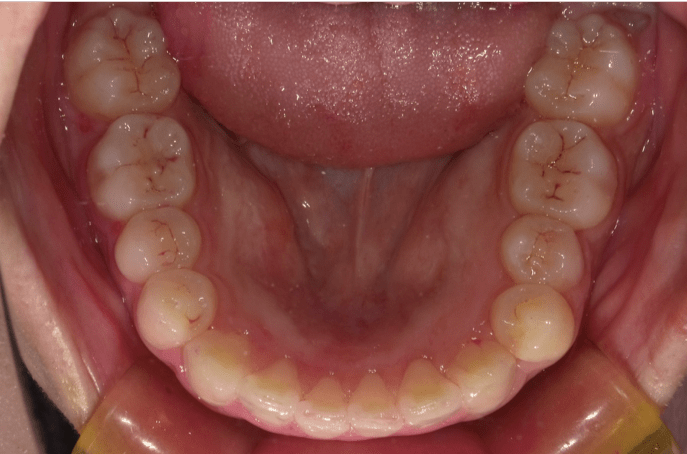

八重歯(重度叢生)

AFTER

担当医コメント

重度の叢生だが、患者の希望により非抜歯での治療を検討した。補綴が多いため補綴に対してのIPRでスペースを確保し、上顎大臼歯の遠心移動を組み合わせ治療することにした。上顎犬歯の歯肉退縮は患者の希望によりこのままで進める事にした。

治療の概要

年齢/性別

40歳 女性

主訴

噛み合わせ八重歯が気になる。上顎の歯が内側に入っているのが気になる

リスク

歯肉退縮が起こる可能性がある。

歯肉退縮を起こしている部位がより進行する可能性がある。

費用

85万円(矯正費用)

期間

2 6 ヶ月